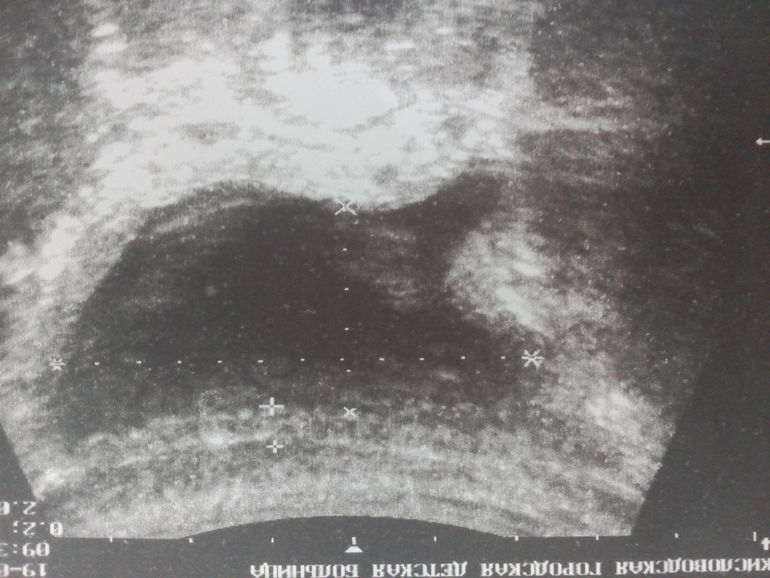

Спасибо, сегодня сделали опять узи, посмотрите что это выпирает в мочевом. заранее спасибо Вам.

К сожалению снимок малоинформативен